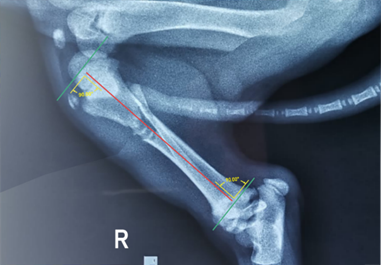

Para la OPMI se optó un implante que abarco la longitud del hueso, se requirió de una placa de bloqueo que se extendió desde la región de la metáfisis proximal hasta la región de la metáfisis distal7. Con la placa radiográfica de la vista lateral medial del miembro posterior derecho, se digitalizo y realizó la planificación pre operatoria de forma virtual. Esta imagen se llevó al programa de vectores CorelDRAW versión X5 para el diseño digital.

En la opción recortar imágenes nos permitió quitar y girar partes para formar la imagen, se alineo el eje central de la tibia tomando en cuenta desde la parte proximal hasta distal seguida del ángulo que forma 90° en la parte proximal se trazó una línea transversal desde la superficie del tubérculo hacia la área intercondilar caudal de la tibia y en su parte distal se trazó una línea transversal desde el borde de la cóclea de la tibia hacia maléolo lateral formando un ángulo de 90° (Figura 2) tomamos de referencia el centro de rotación de la angulación (CORA) para realizar estos trazos del eje central y ángulos.

El implante que se optó, fue del sistema PRCL-M de placa de bloqueo de 9 mm (BlueSAO). La plantilla digital nos ayudó a nivel virtual a definir el tamaño de longitud que abarcara en la tibia fracturada y el implante de bloqueo que se seleccionó para soportar la carga, se consideró el peso y nivel de actividad del paciente. Por otro lado, las placas de bloqueo actuaron como fijadores internos y, por lo tanto, no desplazaron los segmentos óseos de la fractura. Se aplicó 6 tornillos de bloqueo 3 en cada extremo de la fractura parte proximal y distal. La planificación virtual tomo mucha importancia en esta etapa, nos prevé las posibles complicaciones y ajustes a realizar previo al procedimiento de la intervención quirúrgica de OPMI (Figura 3).